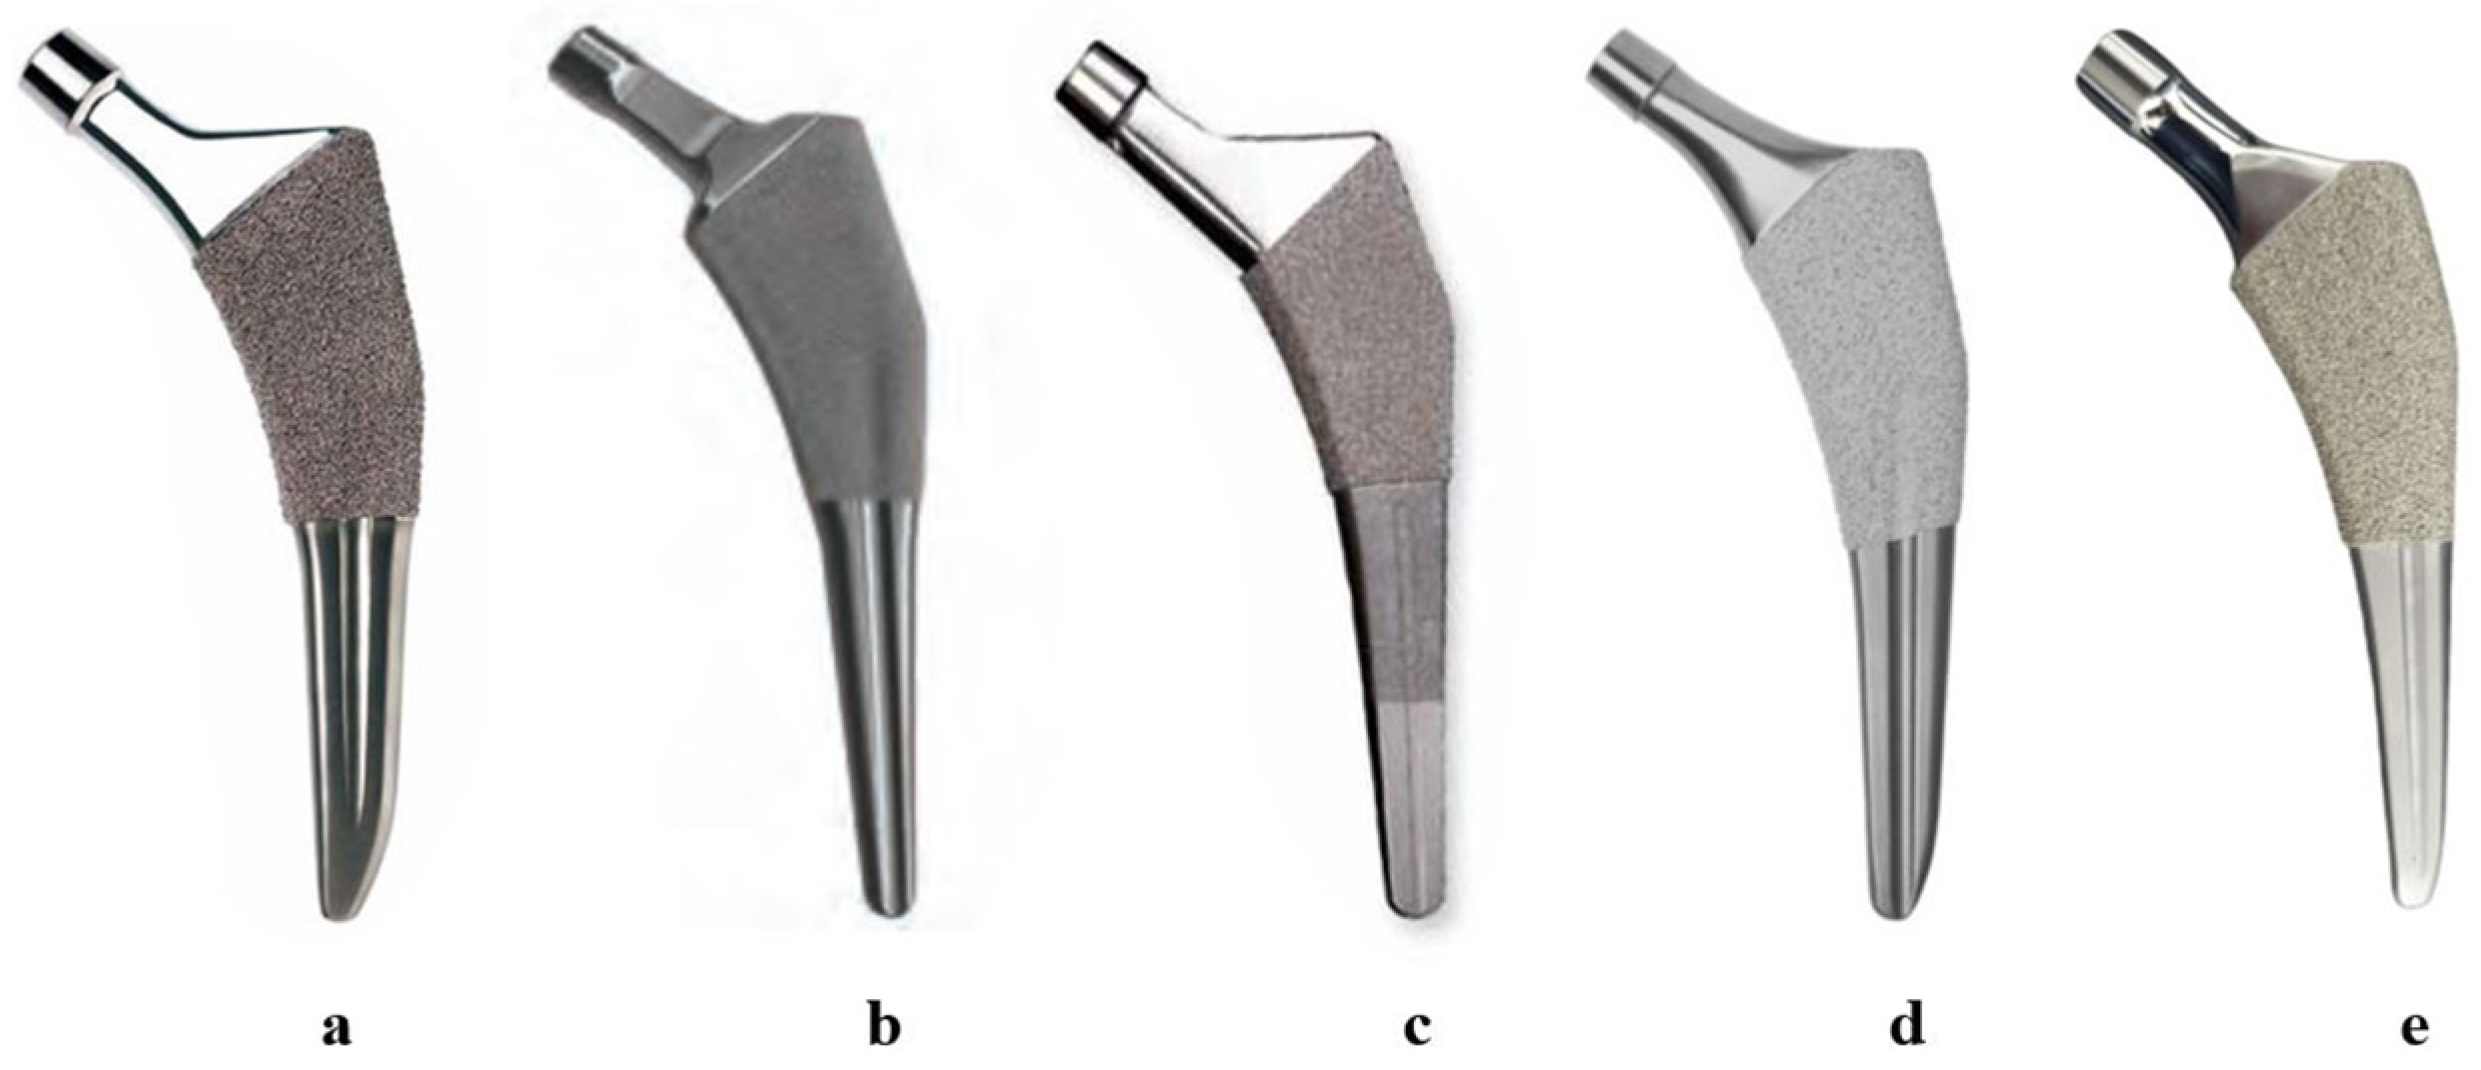

2.4. Femoral Stems for Evaluation